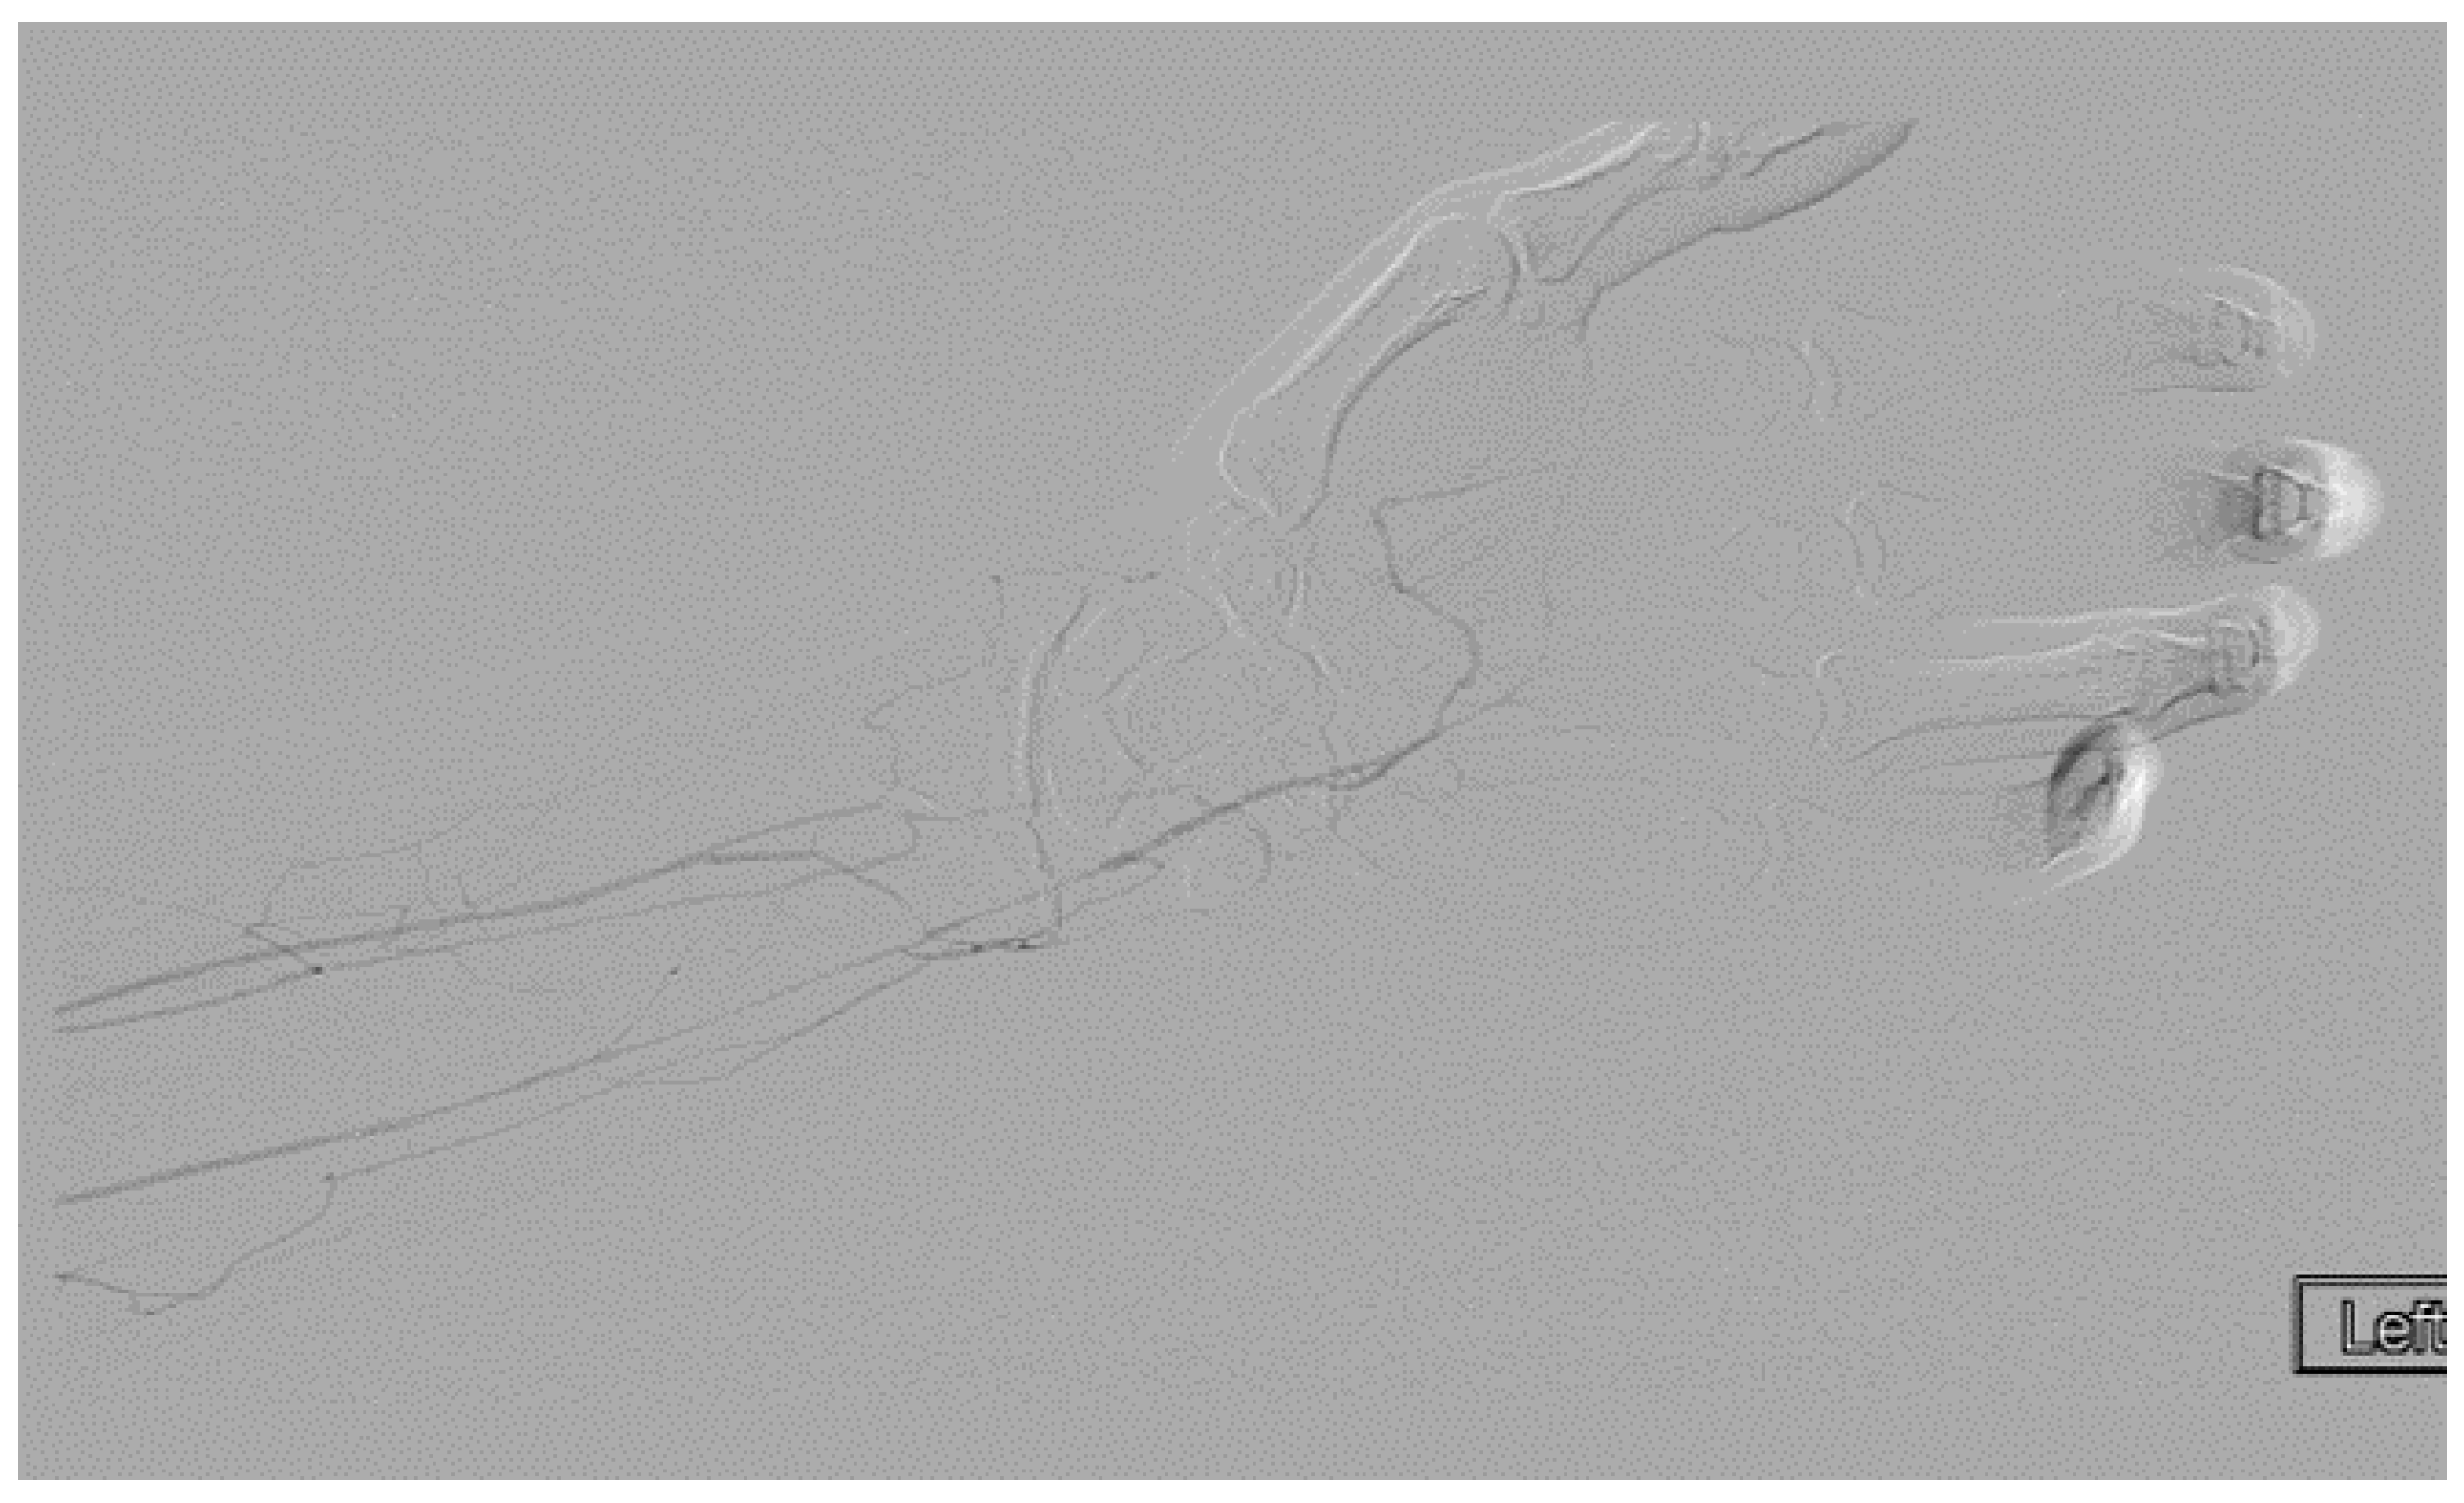

She underwent venography of the right arm venous system which revealed a 70–80% stenosis of the right subclavian vein in neutral position (Figure 1 and Figure 2). The vein was completely occluded in stress position. This was confirmed with intra-vascular ultrasound (IVUS). On IVUS measurements, the neutral position yielded a 74.4% stenosis while the stress position yielded 100% total occlusion (Figure 3 and Figure 4). It was noted that the contralateral vein appeared compressed in the costochondral space as well, though she was asymptomatic.

Figure 1.

Venogram of a Paget-Schroetter patient in the stress position demonstrating significant stenosis of the right subclavian vein.

Figure 2.

Venogram demonstrating a right subclavian vein that is nearly occluded while in stress position.